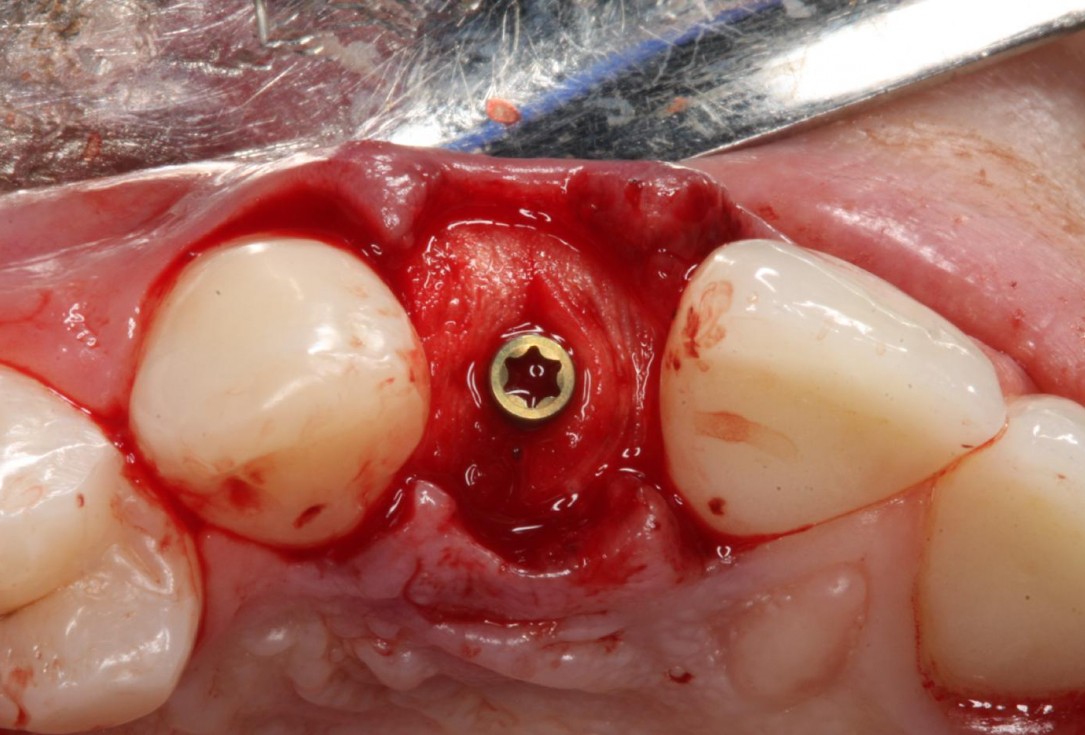

4/12 - Rehydration of mucoderm® and cut to size and shapeSoft tissue thickening at immediate implant placement and GBR with mucoderm® and maxgraft® - Dr. A. Puisys

5/12 - Covering of immediate placed implant and augmentation with maxgraft® granulesSoft tissue thickening at immediate implant placement and GBR with mucoderm® and maxgraft® - Dr. A. Puisys

6/12 - Horizontal and vertical soft tissue augmentation with mucoderm®Soft tissue thickening at immediate implant placement and GBR with mucoderm® and maxgraft® - Dr. A. Puisys